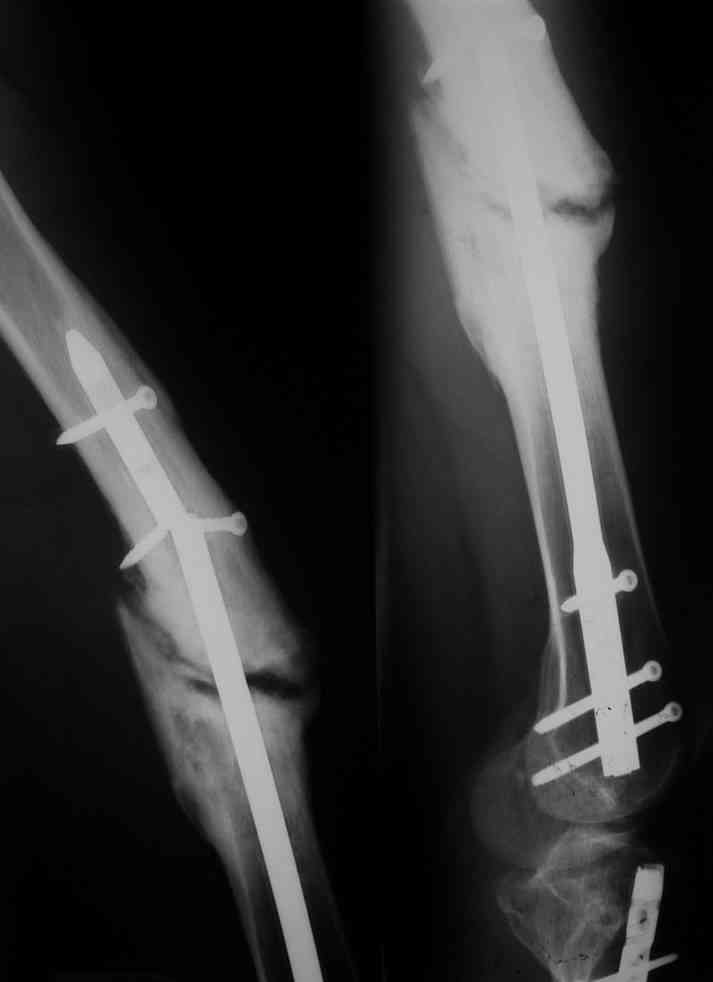

Одной рентгенограммы недостаточно, чтобы планировать подобную операцию. Вот похожий случай, который пришлось оперировать 3 мес. назад. Тоже короткий гвоздь. Шляпки винтов проксимального фрагмента полностью погружены в костную ткань, чего уже достаточно для необходимости обнажения этой зоны. У этого же больного оказались полностью разрушены шлицы 2-х дистальных винтов, так что и там нужно было "открываться".

Рентгенограммы все в наличии, просто не было времени их обработать , но я думаю что представленная рентгенограмма отражает основные моменты.Случай очень похож, точнее

ошибка -короткое плечо штифта в дистальном или проксимальном отломке.

Большей ошибкой явилась длительная статическая фиксация отломков и отсутствие своевременной динамизации. Проще говоря, пациент ходил на конструкции, которая рано или поздно не выдержала циклической нагрузки и сломалась по тонкому месту.

Это произошло бы с меньшей вероятностью, если бы нагрузку своевременно перенесли на костные отломки, которые изо всех сил пытались воссоединиться (о чем говорит наличие неслабой мозоли), да мешала распорка в виде блокированного статически гвоздя.